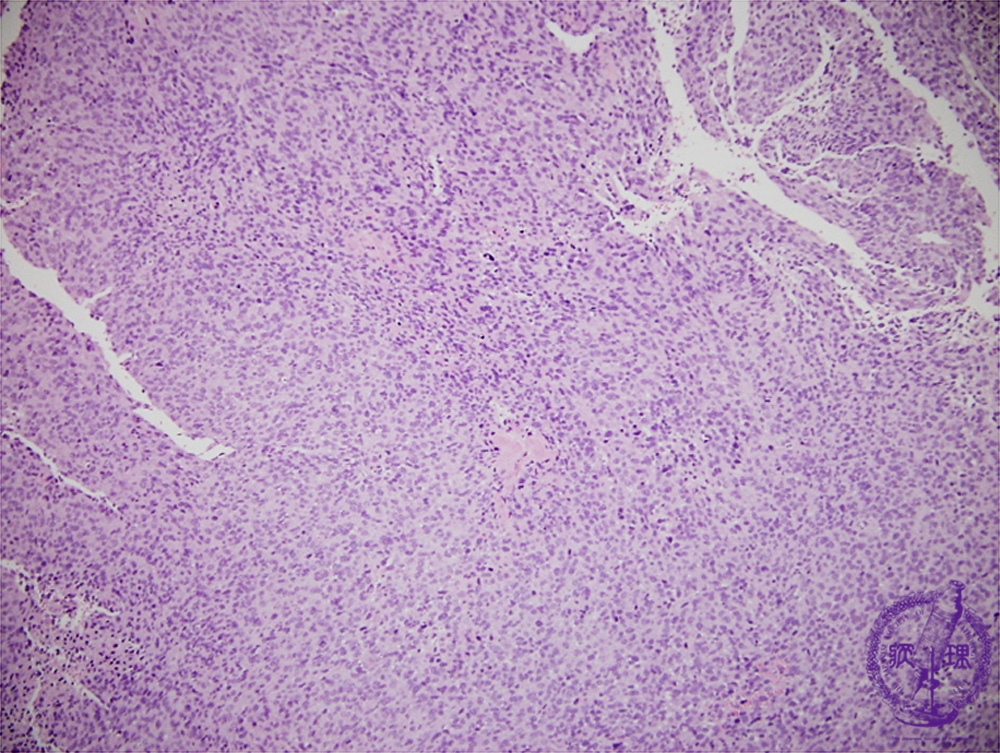

• (2)Malignant peripheral nerve sheath tumor(MPNST)

Microscopic findings (H.E. low power view): Spindle-shaped tumor cells proliferated without forming particular structures.